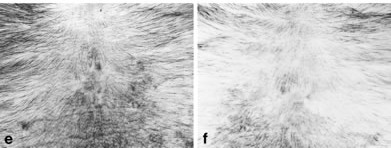

安慰劑治療:e為實驗前,f為實驗後:四個月後,沒有毛髮再生的情況。